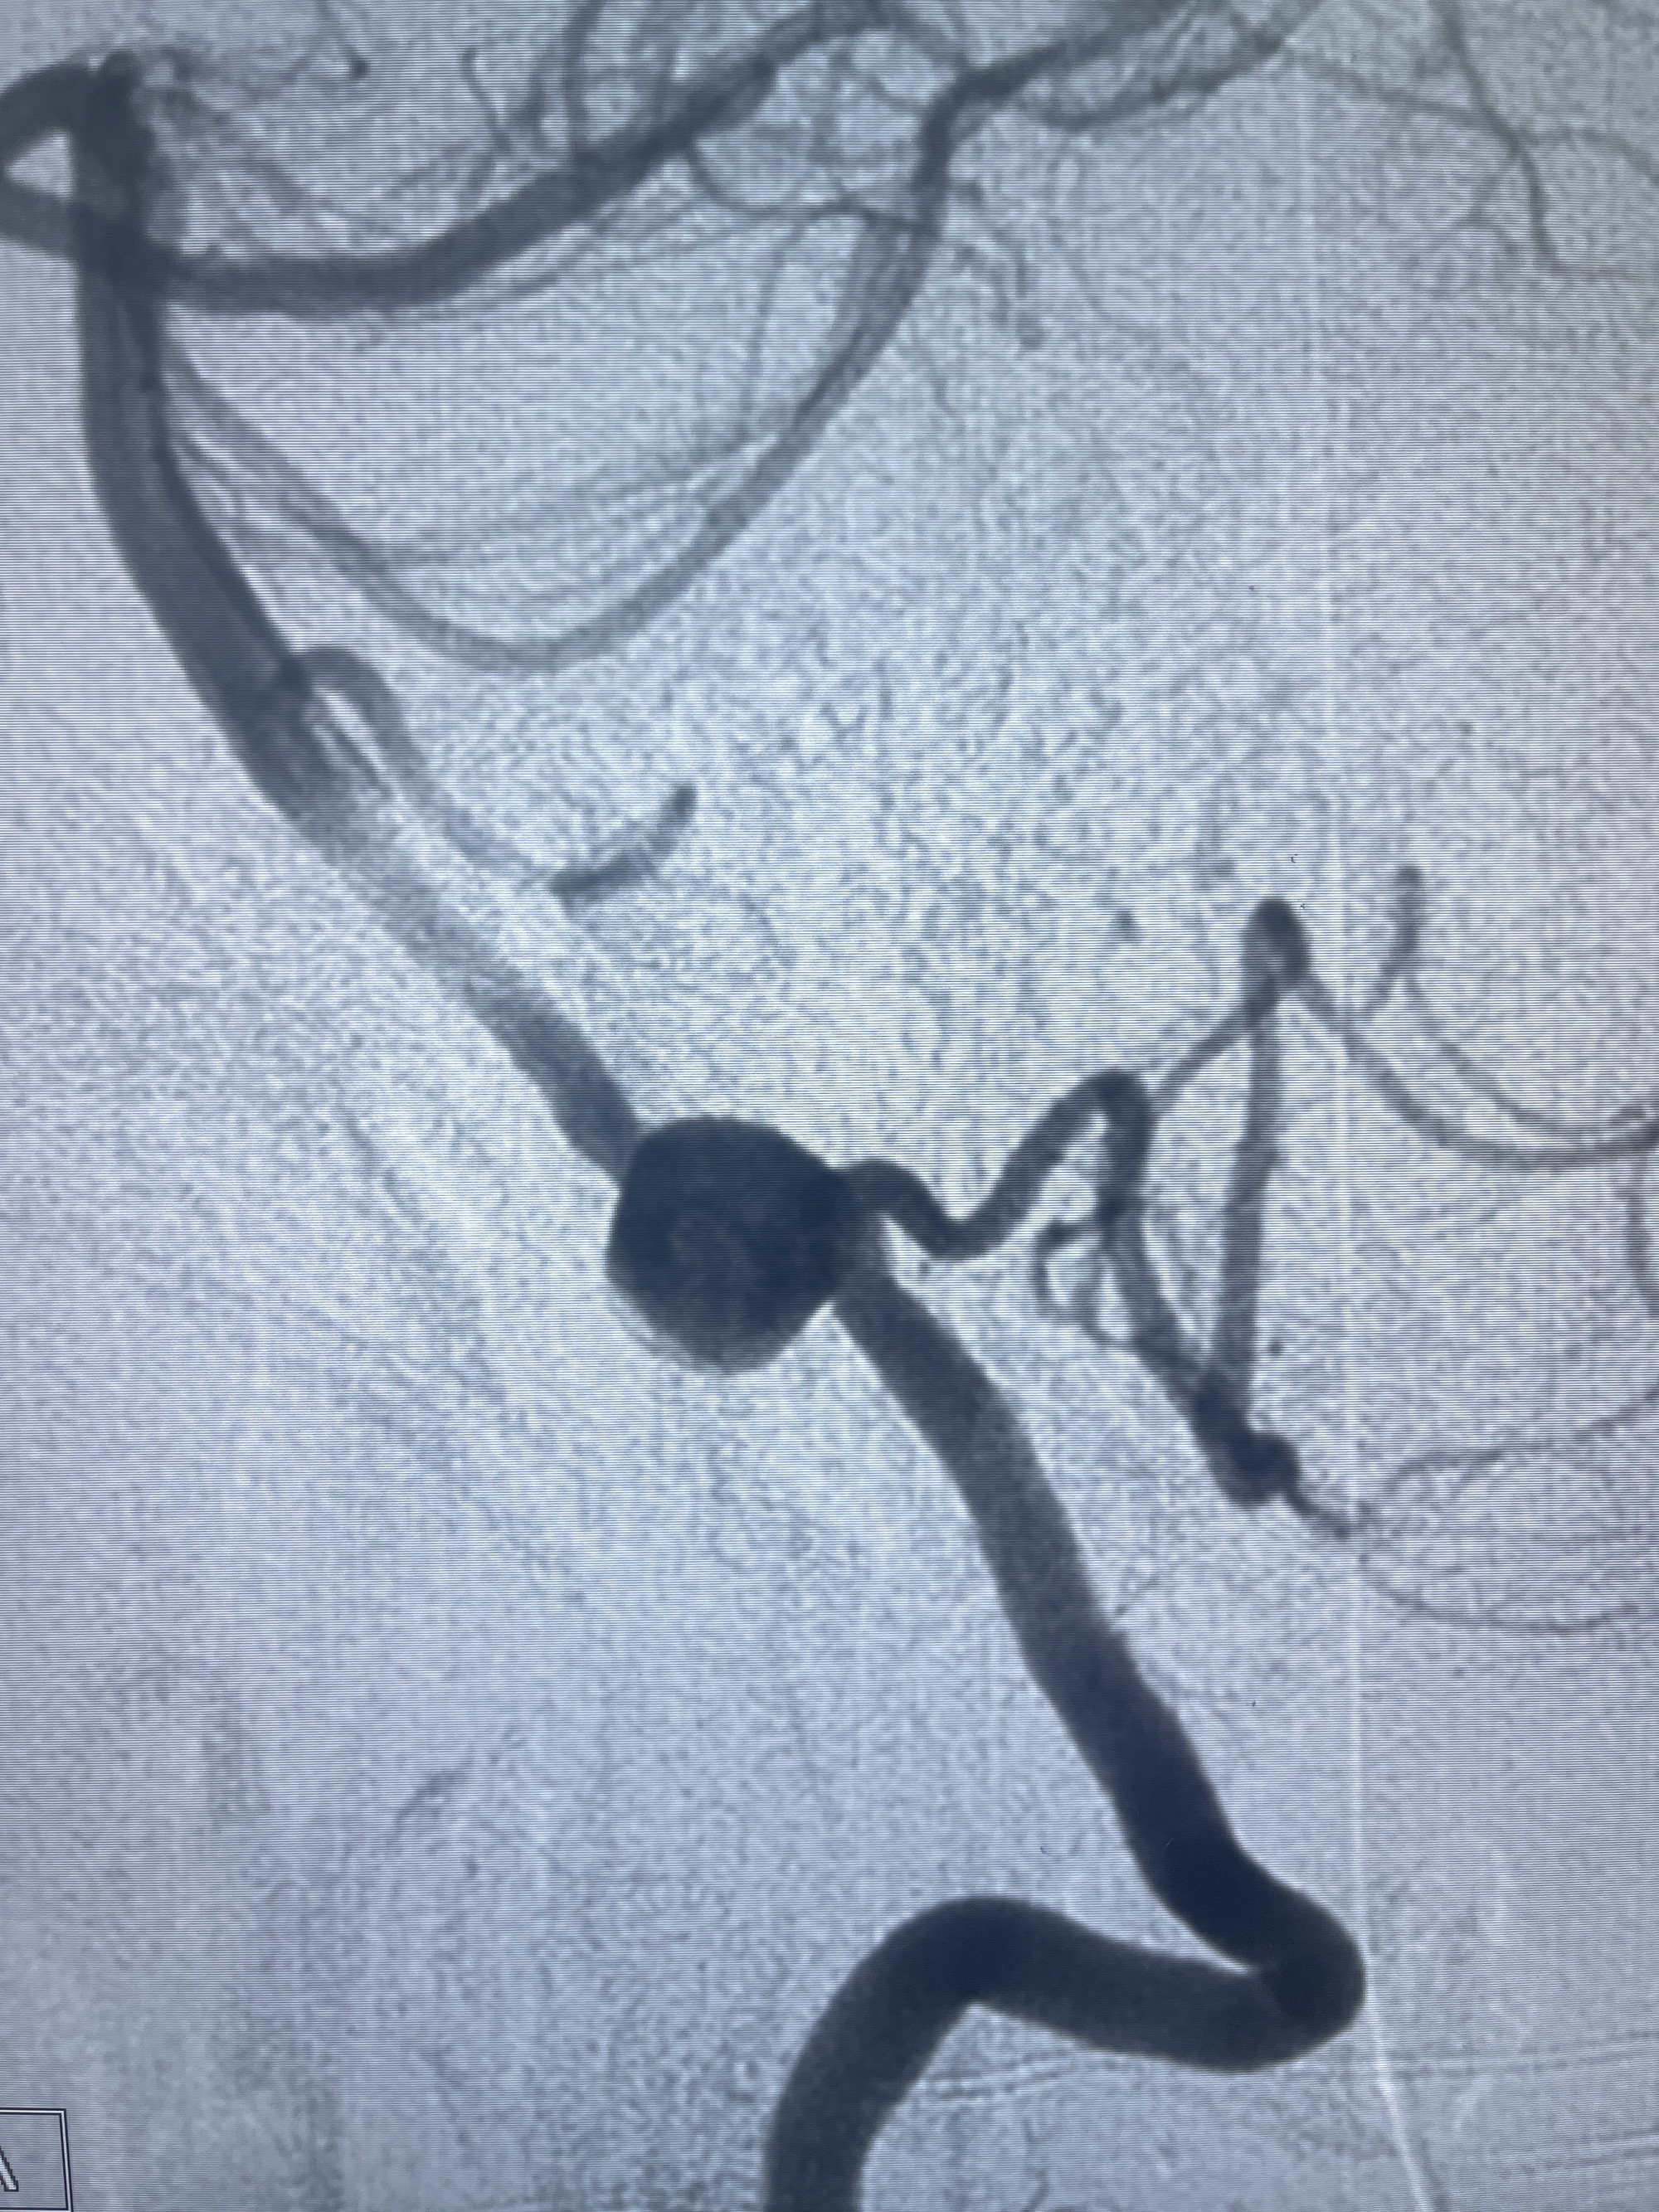

202.04.28脑血管造影:右侧大脑后动脉远段闭塞,右侧椎动脉V4段可见“囊状造影剂填充影”,大小7.64*7.65mm,可见PICA由动脉瘤发出;

1.普通支架辅助弹簧圈栓塞?

2.密网支架辅助弹簧圈栓塞?